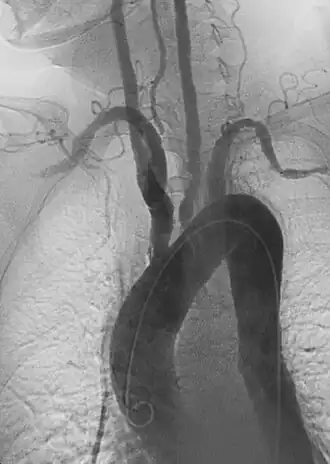

| Angiografia anterior de aorta e grandes vasos com estenose. | |

Durante o exame físico uma diferença entre os pulsos radiais esquerda e direita podem ser percebidos, geralmente um dos pulsos está ausente e o outro aumentado. A estenose dos ramos da aorta afetados pode ser auscultada. Estudos de imagem (como ressonância magnética, raios-X e angiogramas), que mostram a localização e a gravidade da inflamação e aneurismas nas artérias.[6]